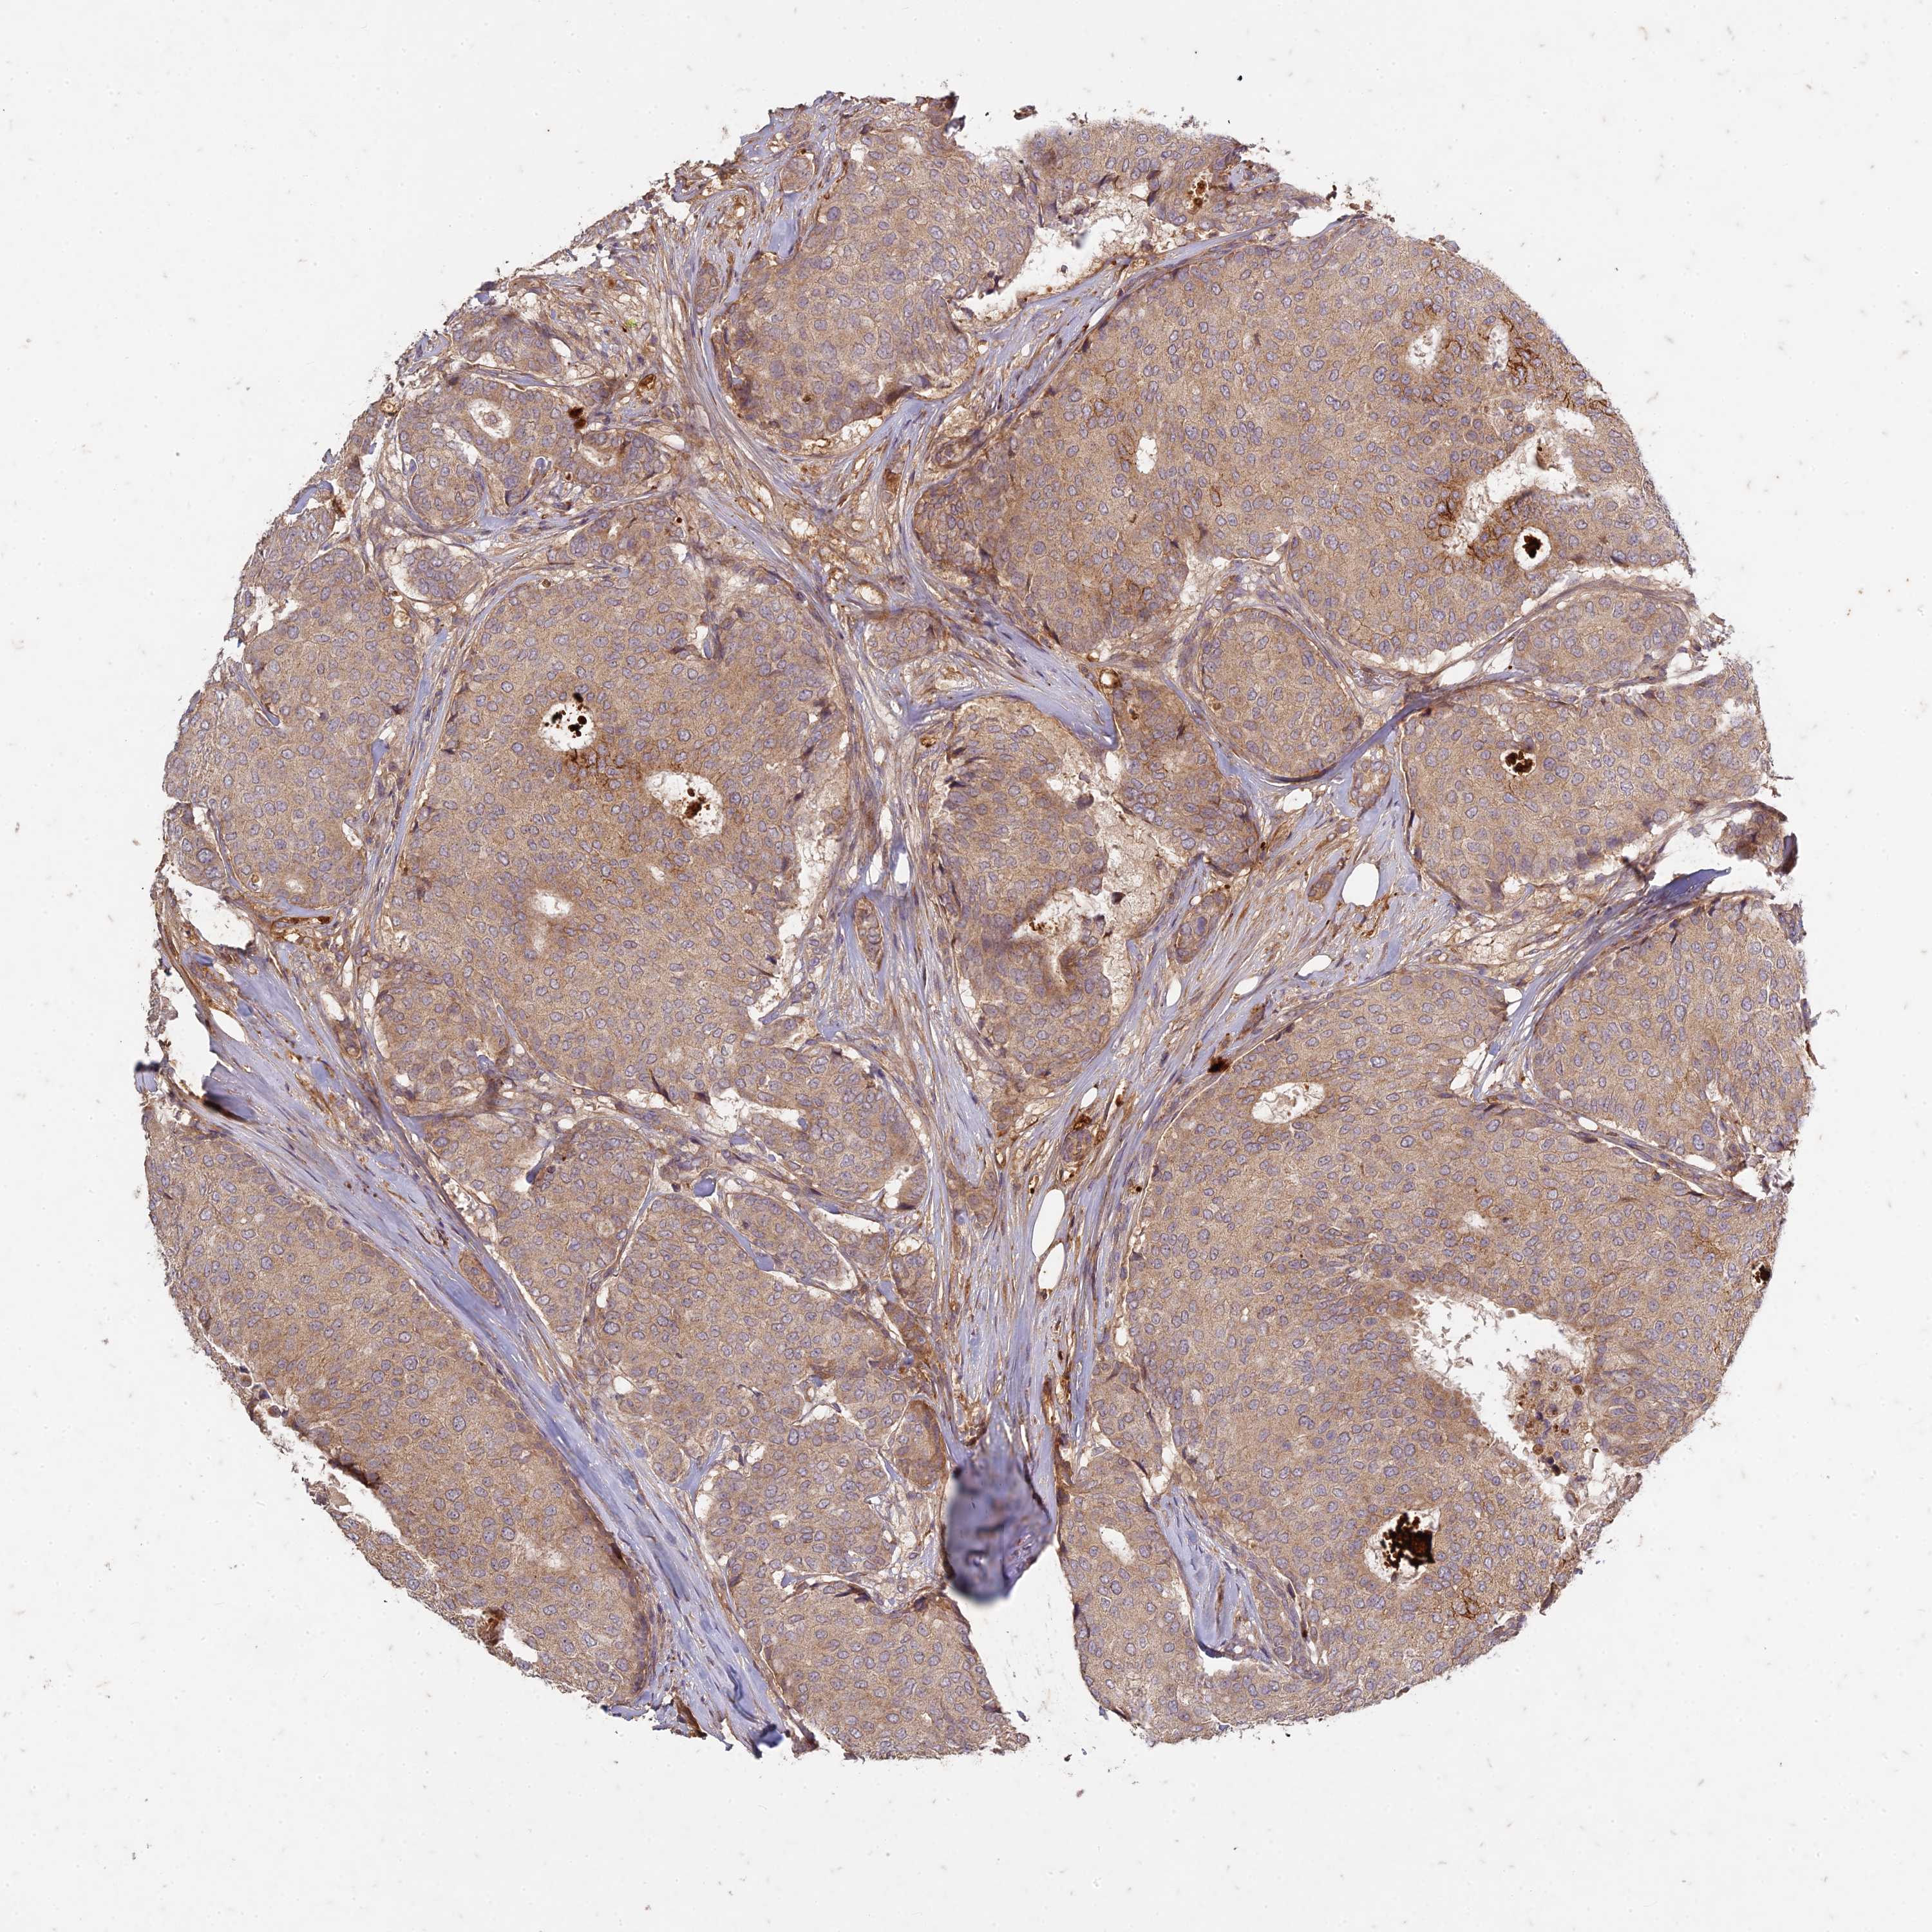

CANCER BREAST CANCER Show tissue menu

BRCA TCGA BRCA VALIDATION PROTEIN EXPRESSION